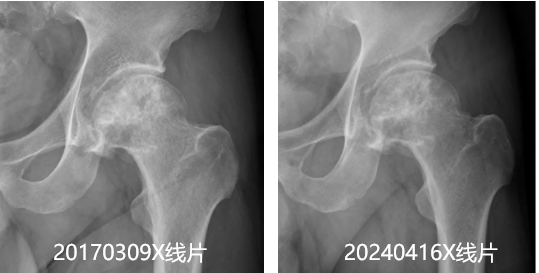

近日,长期在苏州工作生活的睢宁籍股骨头坏死患者王先生,专程前往徐州市中医院介入科进行复查。经过一系列摄线片、及检查,结果显示王先生的左股骨头坏死情况较七年前不仅...